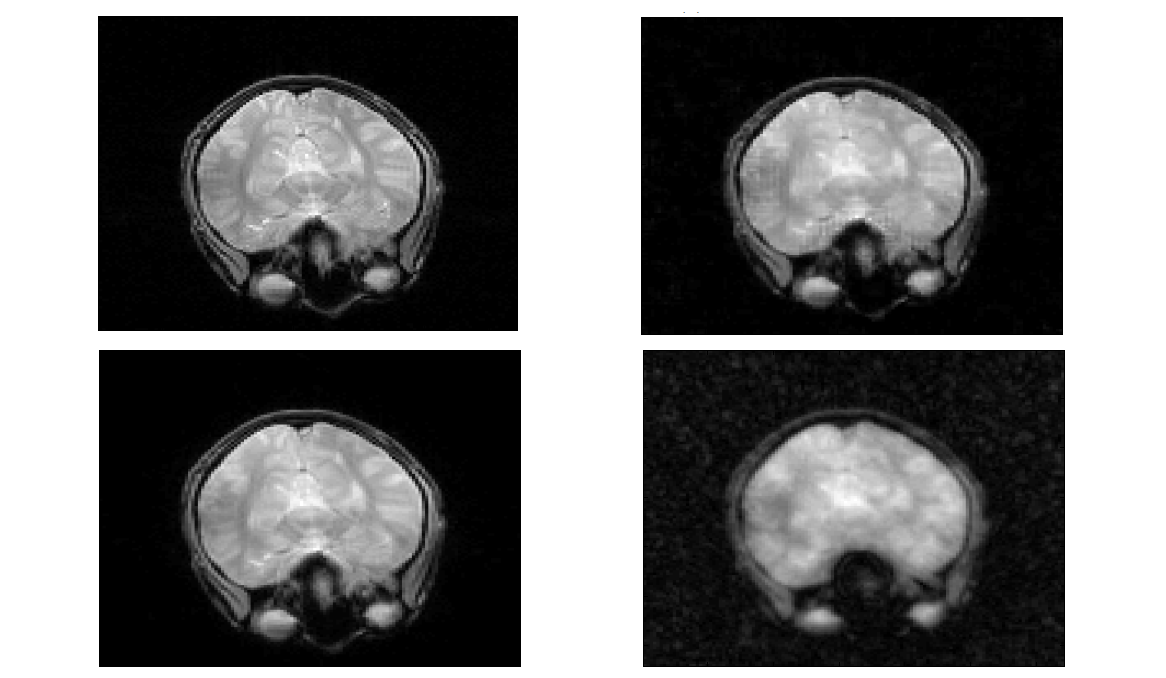

In some medical imaging applications, e.g. MRI, signals have to be recovered from a finite set of measurements. The method of taking those measurements, and thus the representation system used to model this process, is usually mostly fixed. However, the reconstruction system can be chosen freely. By using extra information about the signal to chose the system carfeully the reconstruction can be optimized. If the sizes of the sampling and reconstructing systems are allowed to vary independently of each other the setting is called Generalized Sampling.

Fourier sampling systems and a reconstruction system of compactly supported shearlets have been shown to allow for a stable reconstruction. Moreover, their quotient, the so called stable sampling rate, is almost linear. The proposed method using shearlets outperformed the wavelet approach and a simple Fourier inversion in numerical tests with MRI data.